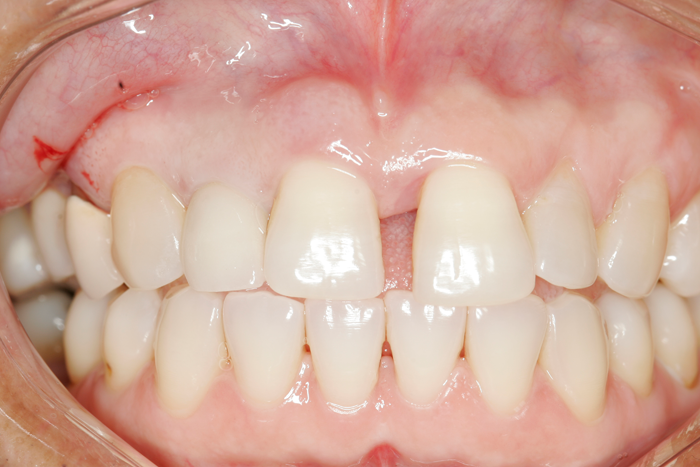

Patient’s teeth after six weeks of Perio Tray usage.